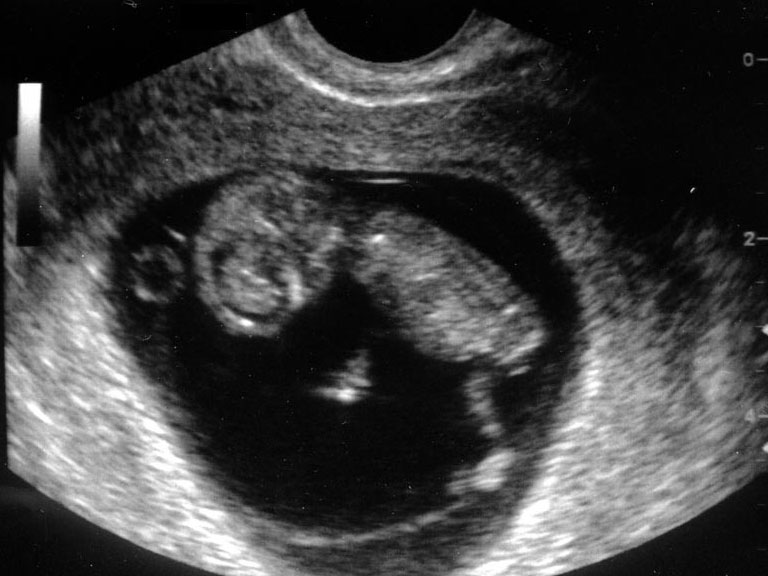

1분기 (착상부터 임신 14주까지)

1. 임신낭 위치

2. 배아 존재 확인

3. 배아의 정둔장 체크 (즉 배아의 머리끝부터 엉덩이 끝까지 길이)

4. 배아나 태아의  생존 여부 즉 심박동 유무와 횟수 확인

5. 배아나 태아의 수 확인

6. 자궁과 그 부속기인 난소등 검사